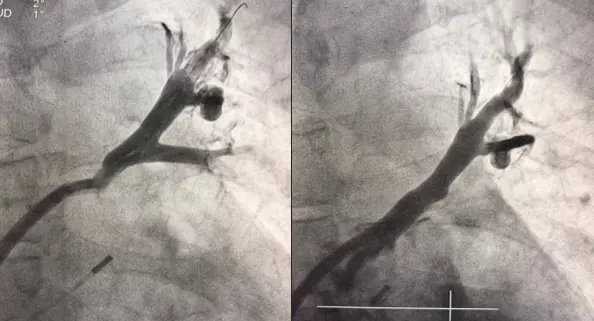

Рисунок 2. Левая верхняя легочная вена до и после стентирования. Исходная ангиография представлена после выполнения дилатации в связи с исходной окклюзией.

Вмешательство проводилось через бедренный венозный доступ под местной анестезией. Основная сложность операции заключалась в полной окклюзии обеих легочных вен и необходимости точной навигации инструментов в условиях ограниченной визуализации. После реканализации поражённых участков были имплантированы стенты, обеспечившие надёжное восстановление просвета сосудов и полноценный венозный отток из лёгких.

В результате кровоток по левой верхней и левой нижней легочным венам полностью восстановлен. Состояние пациента стабилизировалось, одышка регрессировала. В настоящее время пациент чувствует себя хорошо.